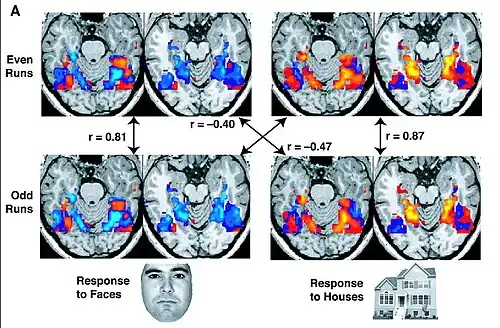

fMRI images from a study showing parts of the brain lighting up on seeing houses and other parts on seeing faces

These fMRI images are from a study showing parts of the brain lighting up on seeing houses and other parts on seeing faces. The 'r' values are correlations, with higher positive or negative values indicating a stronger relationship (i.e., a better match).